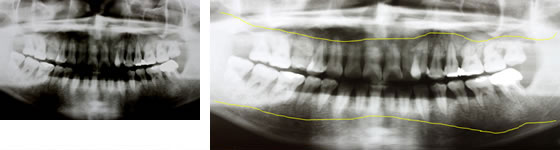

重度の歯周病の方の骨の状態

重度に歯周病が進行した方の骨の位置です。歯が骨に1/3以下しか入っていません。

状態:中度(P2)、重度(P3)